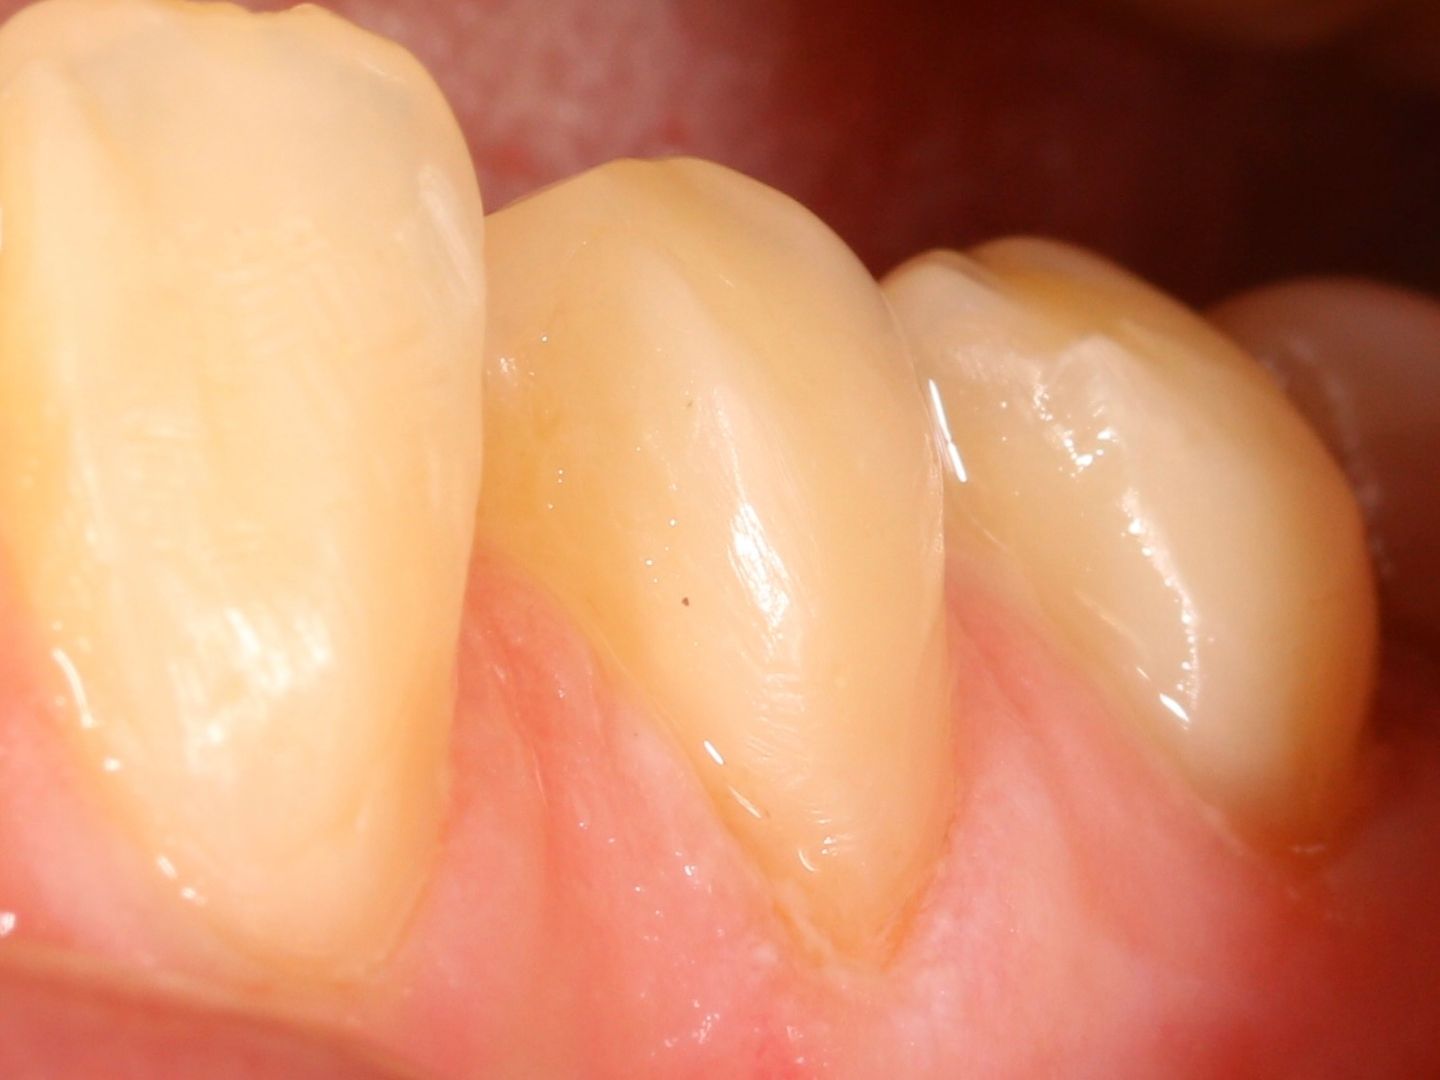

• Восстановлением разрушенных зубов с последующей подготовкой их под ортопедические конструкции.